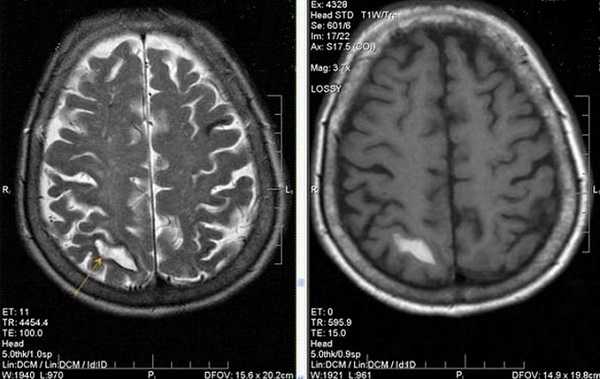

МР-снимок показывает дистрофические изменения белого вещества вокруг желудочков мозга, характерные для хронической ишемии (лейкоареоз)

Нейровизуализационные методы: КТ, МРТ головного мозга, МР-ангиография (артерии и вены головного мозга ), при необходимости рентгеноконтрастная церебральная ангиография. Нейровизуализация позволяет исключить другие заболевания (опухоль, гидроцефалию) и подтвердить сосудистый характер нарушений. Предпочтительнее МРТ головного мозга, на которой выявляются характерные для хронической ишемии мозга изменения:

- лейкоареоз — изменение белого вещества вокруг желудочков головного мозга (на рисунке 1, белое свечение вокруг желудочков);

- лекоэнцефалопатия — поражение белого вещества головного мозга (на рисунке 1 и 3, светлые участки в подкорковом веществе);

- малые инфаркты, ишемические инсульты (рисунок 3);

- множественные микрокровоизлияния (рисунок 2 — темные участки);

- атрофия коры головного мозга.

Существует зависимость между типом и выраженностью морфологических изменений мозгового вещества и стадией заболевания [4] [6] .